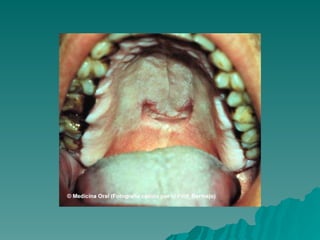

Fase 2: Sífilis primária

 Aparece um lesão rosada ou

Aparece um lesão rosada ou

ulcerada, geralmente indolor que

podendo passar despercebida

(no pênis, vagina, boca ou ânus).